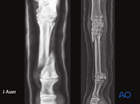

Metacarpals/-tarsals III: Proximal simple fractures